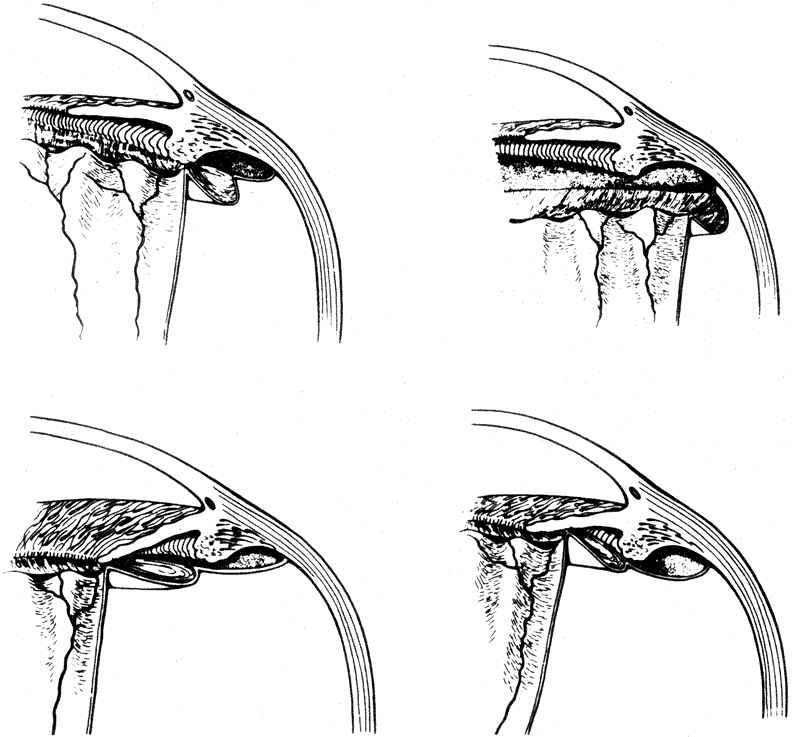

The pathogenesis of macular holes has been controversial for some time. Initial reports suggested an association with hormonal changes, disorders of the retinal pigment epithelium, and retinal thinning, as well as systemic vascular diseases and cystic retinal degeneration.84 However, as the ability to examine the vitreous has improved, the central role of the vitreous in the pathogenesis of macular holes has become increasingly clear. Early observations suggested that shrinkage of the vitreous fibers that extend through the vitreous base may account for macular hole formation.85 Subsequent studies have suggested that the shrinkage of the prefoveal vitreous cortex is the central and initiating event in the formation of macular holes. Gass' initial classification of macular holes proposed in 1988 was the first classification attempting to explain the clinical presentation and pathophysiology in the development of full-thickness macular holes. This classification was reappraised and updated in 1995 and stratifies the formation of macular holes into four separate stages86 (Fig. 11). Although these four stages remain useful for the clinical description of macular hole formation, more recent imaging techniques using the scanning laser ophthalmoscope, the retinal thickness analyzer, and OCT have caused many investigators to reconsider the pathogenesis of macular holes.

Fig. 11. Updated diagram of proposed development of idiopathic macular holes according to Gass. (Gass JDM: Reappraisal of biomicroscopic classification of stages of development of a macular hole. Am J Ophthalmol 1995;119:752)

Stage 1

The earliest clinical sign of impending macular hole formation is the presence of a 100- to 300-micron yellow spot in the fovea in association with flattening of the normal foveal depression and the absence of vitreofoveal separation (Fig. 12). Gass86 postulates that this is the result of tangential traction because of prefoveal vitreous contraction, which results in a foveolar detachment. As the foveal retina elevates to the level of the surrounding thick perifoveal retina, the retinal receptor layer is stretched or elongated, and thinning of the foveolar retina around the umbra causes a change from a yellow spot to a small, donut-shaped, yellow, right lesion (stage 1-B, impending macular hole, Fig. 13). This change from a yellow spot to a ring is followed by a break in the continuity in the receptor cell layer at the umbra, structurally the weakest point in the retina. The retinal receptors, the radiating nerve fibers, and the xanthophyll retract intrinsically beneath the contracted vitreous cortex, and the yellow ring enlarges and develops a more defined central semitranslucent zone (stage 1-B lesion, occult macular hole). The change from a stage 1-B impending hole to a stage 1 occult hole cannot be detected biomicroscopically.

Stage 2

Stage 2 macular hole forms when a dehiscence occurs in the inner retinal layer of a stage 1-B hole. It may be difficult or impossible to detect the transition between a stage 1-B and a stage 2 macular hole with biomicroscopy. OCT, however, can demonstrate the inner retinal dehiscence and the adherence of the posterior vitreous cortex to the inner retinal break.87,88

Stage 3

As the size of the stage 2 hole enlarges, the yellow ring also enlarges, gradually becoming gray and coinciding with the area of the retinal detachment that surrounds the hole (Fig. 17). Stage 3 holes average 460 to 500 microns in size with a retinal defect, no Weiss ring, and a rim of elevated retina. They clinically can present with prefoveolar opacities represented by a pseudo-operculum. They also may present without prefoveolar opacities. As the hole enlarges, visual acuity drops to a median of 20/200. Most stage 3 holes remain stable with no progression of visual loss or foveal detachment. Over months to years, pigment epithelial alterations, deep pigmentation, and drusen formation may occur. Fine epiretinal membranes occur in approximately 30% of stage 3 eyes.82

Stage 4

Posterior vitreous separation from the optic disc and macula, as evidenced by a peripapillary vitreous condensation ring on the posterior vitreous cortex (posterior hyaloid), occurs in a minority (30%) of macular holes and is termed stage 4. Earlier studies described PVD in up to 100% of eyes with macular holes. This is likely due to the difficulty in identifying a posterior vitreous separation. Posterior areas of vitreous liquefaction may appear to represent posterior vitreous separation, but the vitreous cortex remains attached (Fig. 19). A peripapillary ring is the only reliable sign of a complete posterior vitreous separation. Sophisticated ultrasound examination of the vitreous and laser biomicroscopy in conjunction with OCT may also be helpful in establishing the presence of a vitreous separation.87,92,93